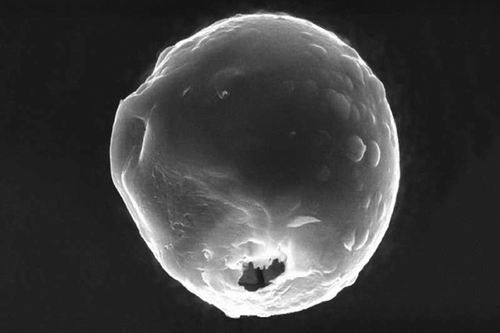

氣體從洞中逸出,為膠囊移動提供動力。 圖片來源:Wu, et al.

熱量還釋放了鎂,而鎂通過與腸液的化學反應,產生了氫氣泡。這種氣體從外殼上留下的2納米的孔中釋放,為腸道周圍的膠囊提供動力,就像微小的氣球在飛行時釋放出空氣一樣。